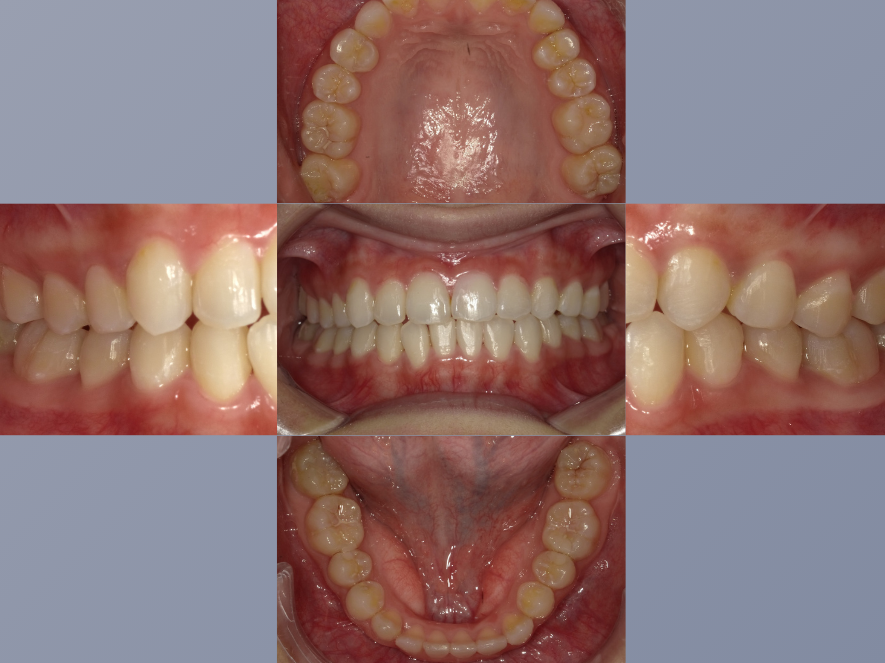

治療前

| 年齢・性別 | 20代・女性 |

|---|---|

| 主訴 | 歯並びが気になる。 |

| 期間 | 2年6カ月 |

| 費用 | 1,452,000円 |